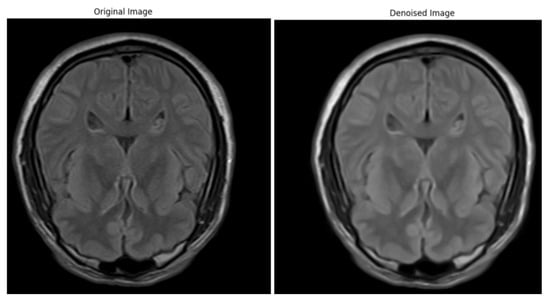

Artifacts and Noise Reduction

Bias Field Correction